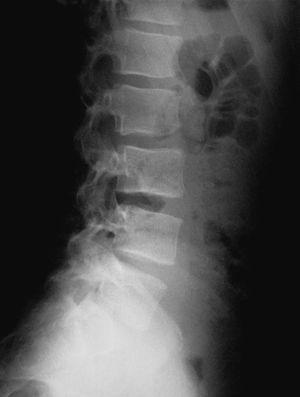

En la visita següent el pacient es presenta amb radiografies que confirmen el diagnòstic d'espondilòlisi L5 unilateral dreta (figs. 1 i 2). D'acord amb el document de consens de la Societat Catalana de Medicina de l'Esport, se sol·licita una gammagrafia òssia planar (GOP) amb tomografia computaritzada per emissió de fotó simple (SPECT). Es decideix continuar amb el mateix tractament i s'assabenta el pacient que serà un tractament a llarg termini.

Figura 2